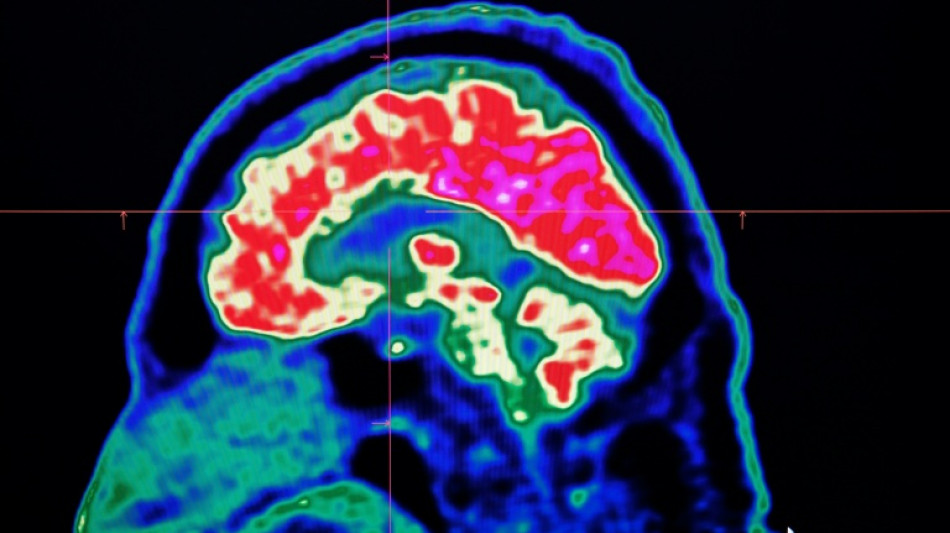

Final report casts doubt on existence of Canada mystery brain illness / Photo: Fred TANNEAU - AFP